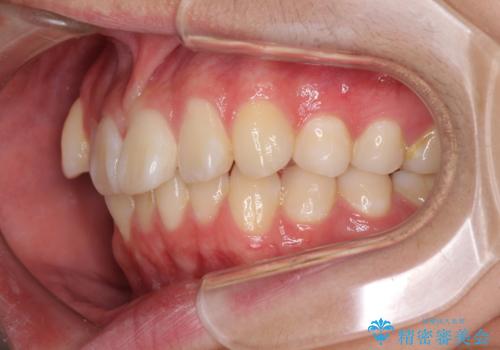

- 八重歯を気にして来院された高校生の患者様です。

ボディーコンタクトの激しい部活動を行っているため、補助装置とインビザラインを用いて、部活動を継続しながら治療を行うこととしました。

八重歯を効率よく改善するため、補助装置を使用して上顎の奥歯を後方に移動させました。

部活動をしながらでしたが、マウスピースをしっかりと装着してくださったので、1年半程度で終了することができました。